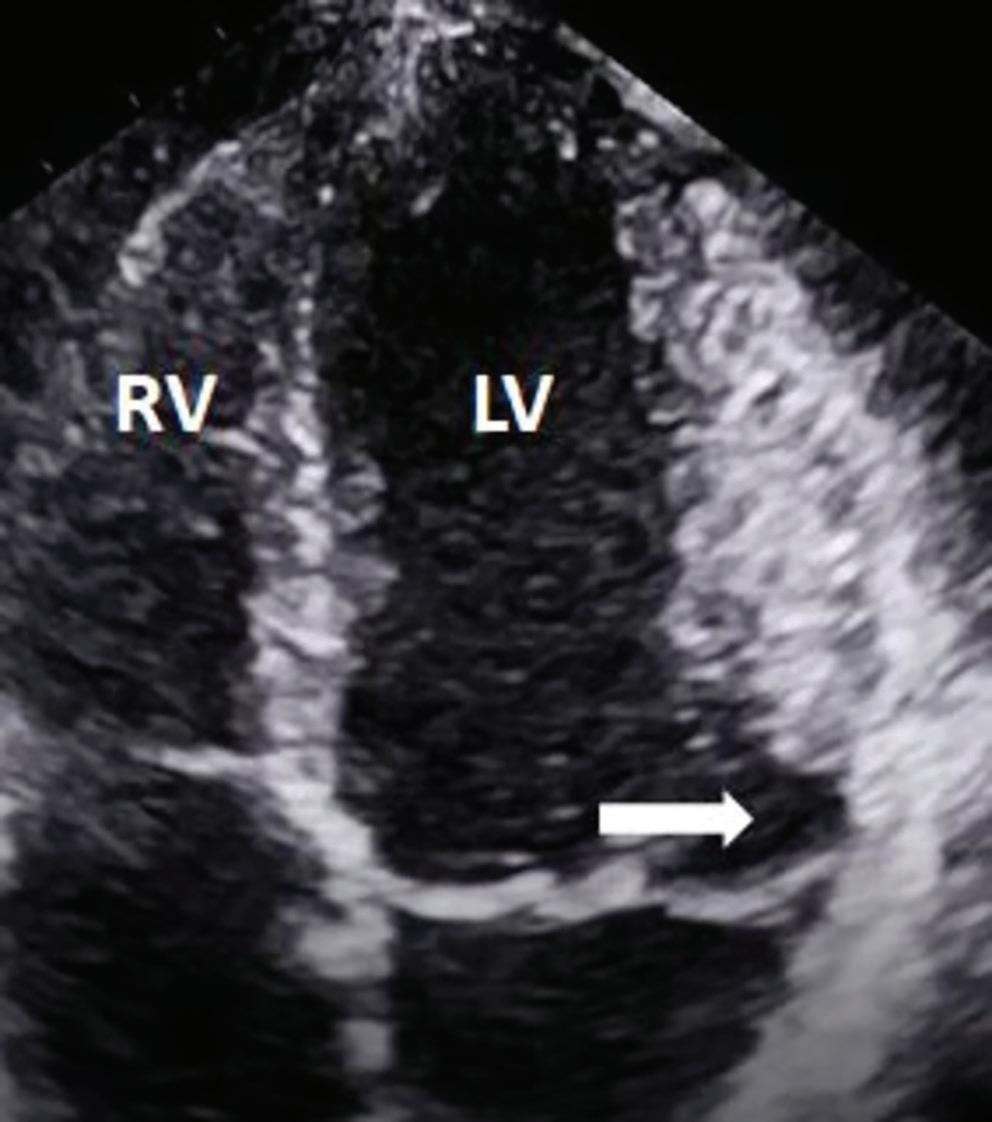

Figure 6: Ventricular Ablation Lesion Assessment

Preprocedural LGE-MRI (1 day before VT ablation)

Ablation points

Post-ablation LGE-MRI (3 months after VT ablation)

Left: 3D reconstruction of the left ventricle with LGE-based colour-coding based on thresholds for dense scar (red, >60% maximum of signal intensity) and border zone (yellow, 40–60% of maximum signal intensity), mapped using ADAS 3D. Shown are the layers at 30% of the transmurality (from endocardial to epicardial). For the post-ablation LGE-MRI (lower panel), an additional 3D reconstruction of the manually defined dark core in red (black arrow) is depicted. Blue lines indicate the plane of the short-axis slices on the right. The ablation points (TactiCath, Abbott Medical) are visualised using a 3D mapping system (EnSite Precision, Abbott Medical). Middle: Overlay of the T1-weighted short-axis slices with the colour-coding described above. The central hypoenhancement dark core of the ablation lesion is manually delineated (red border) to avoid misinterpretation as healthy tissue. Right: T1-weighted short-axis LGE-MRI slices without colour-coding. LGE = late gadolinium enhancement; VT = ventricular tachycardia.